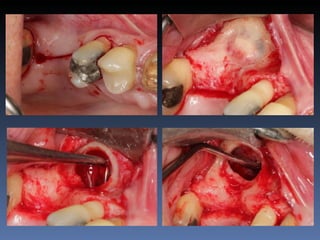

Plano de tratamento: Reabilitação com 1 bloco “onlay”

autógeno proveniente do Ramo de Mandíbula; para

reabilitação futura com implante endo-ósseo.

Espessura Residual

2,5 mm

Defeito Horizontal

Espessura após reabilitação

8,8 mm

Preenchimento de “Gaps”

com particulado ósseo

e

Sutura

Descorticalização   Fixação do bloco “onlay”